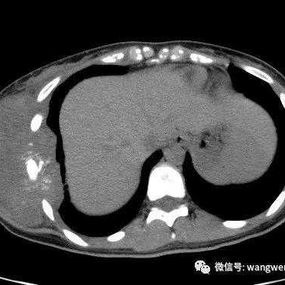

The patient, only 20 years old, developed an egg-sized mass on the right chest wall 6 months ago. Despite conservative treatment, there has been no obvious improvement. More concerning, the mass has continued to grow and now has affected multiple ribs, prompting the patient to urgently seek surgical treatment.

Preoperative Examination

There is a large tumor on the right chest wall, with dimensions of approximately 30x25x20 cm. It is firm, tender to the touch, and has limited mobility. The tumor has already involved the 5th through 8th ribs on the right side.